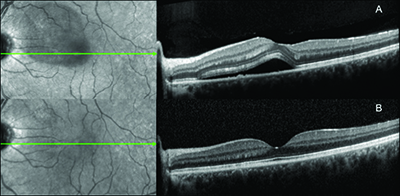

who had consumed eight cups of coffee per day (A) and a follow-up OCT

image (B) three months after the patient stopped consuming caffeine. This

patient had no clinical recurrence of disease.

Figure 1 shows a baseline OCT image of one patient with subfoveal fluid who was consuming eight cups of coffee per day. (Figure 1A) A follow-up OCT image (Figure 1B) three months after the patient stopped consuming caffeine shows reduction of subretinal fluid. This patient had no clinical recurrence of disease.